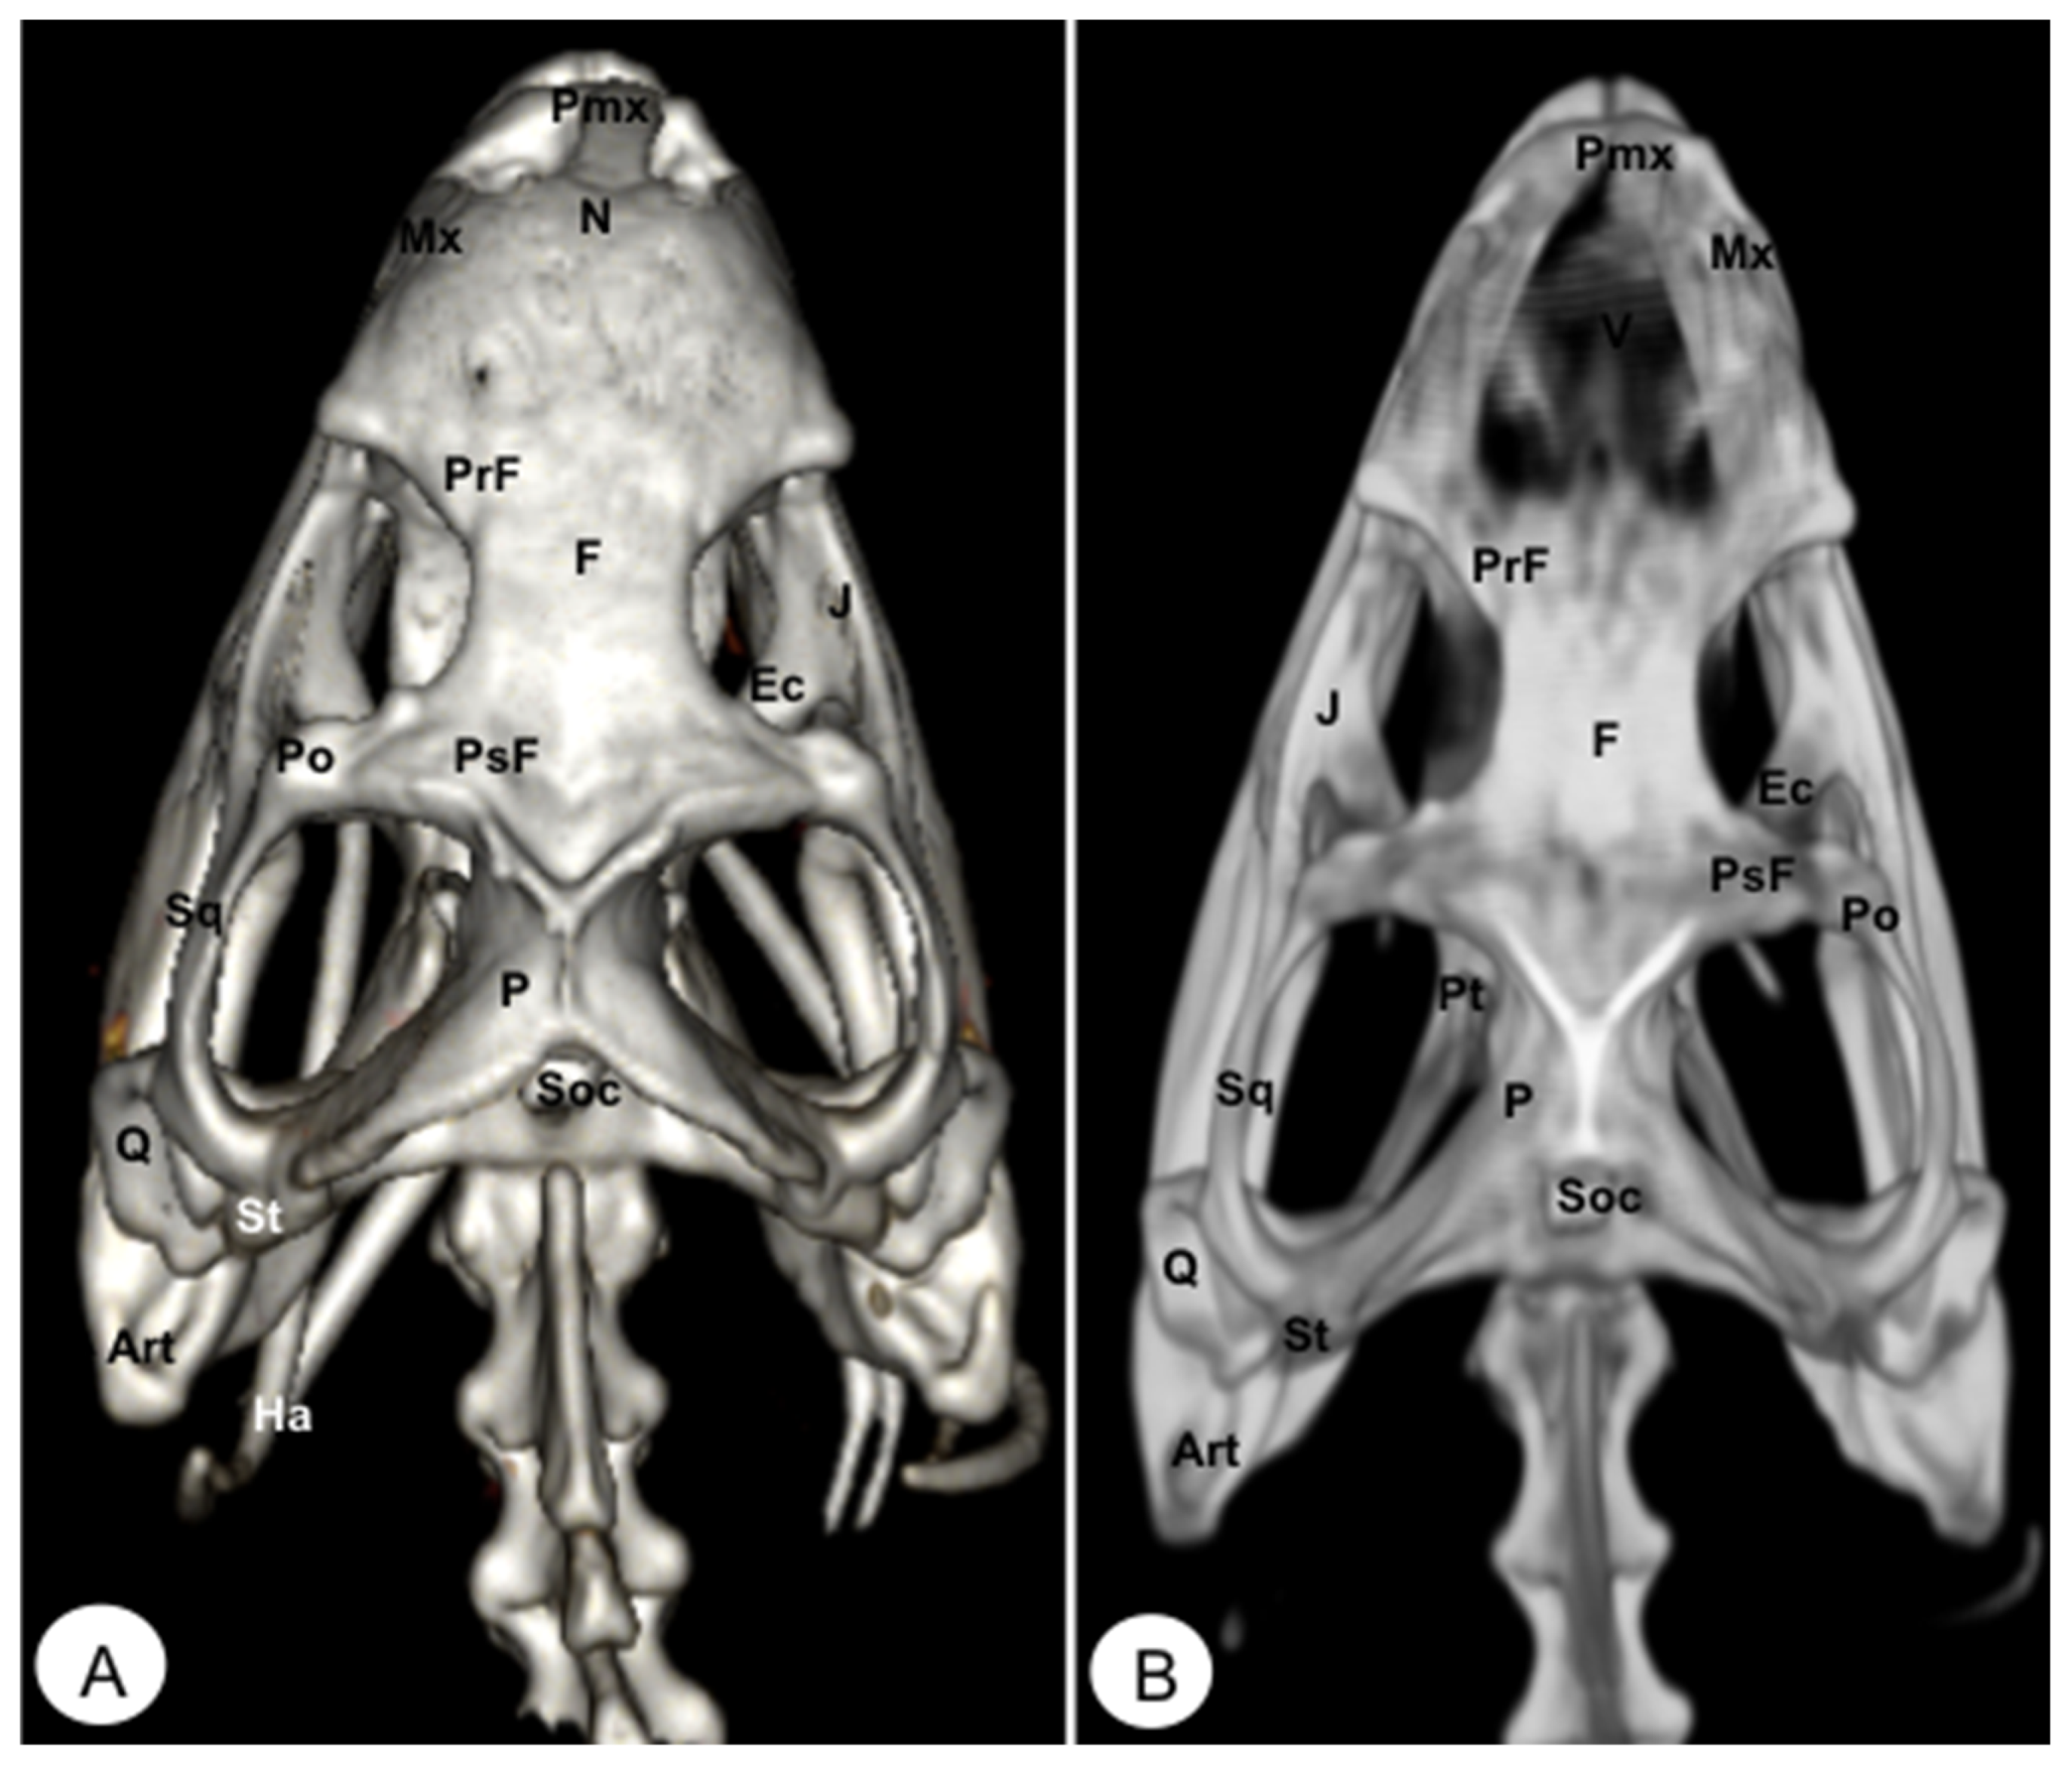

Different rostral, lateral, ventral, dorsal, and caudal VR and MIP images were obtained for better visualization and description of the different bones comprising the head (dermatocranium, neurocranium, and mandibula) of the turtle and the iguana (Figure 2, Figure 3, Figure 4, Figure 5, Figure 6, Figure 7, Figure 8, Figure 9, Figure 10 and Figure 11). We selected images that better matched each other, providing valuable information.

Figure 7. Head of Iguana iguana. (A) Rostral VR image. (B) Rotral MIP image. N: Nasal. Pmx: Premaxillary bone. Mx: Maxillary bone. PrF: Prefrontal. F: Frontal. PsF: Postfrontal. Po: Postorbital. J: Jugal. Q: Quadrate. P: Parietal. O: Orbit. Pt: Pterygoid. Ec: Ectopterygoid. Art: Articular. C: Coronoid. D: Dentary. San: Surangular.

Animals 13 00621 g007

Figure 8. Head of Iguana iguana. (A) Lateral VR image. (B) Lateral MIP image. Pmx: Premaxillary. Mx: Maxillary bone. N: Nasal. PrF: Prefrontal. L: Lacrimal. F: Frontal. PsF: Postfrontal. Po: Postorbital. SO: Scleral ossifications. J: Jugal. Q: Quadrate. Sq: Squamosal. Ec: Ectopterygoid. Pt: Pterygoid. EPt: Epipterygoid. Cp: Cultriform process. PBsp: Parabasisphenoid. P: Parietal. St: Supratemporal. D: Dentary. A: Angular. San: Surangular. Art: Articular. C: Coronoid. Ha: Hyoid apparatus. C1: First cervical vertebra. C2: Second cervical vertebra.

Animals 13 00621 g008